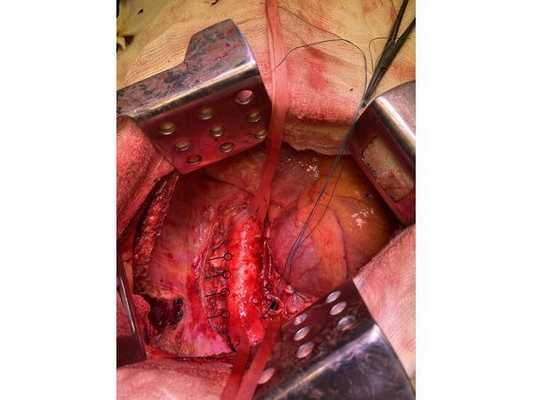

Интраоперационное фото: клипированные межрёберные артерии; аорта на тесёмочных держалках по краям зоны резекции адвентиции; культя главного бронха с провизорными швами при ушивании по Оверхольту

Проведён онкологический консилиум (Клиническая больница № 2 АО ГК МЕДСИ). Решением консилиума рекомендовано первым этапом провести хирургическое лечение в объёме нижней лобэктомии (удаления доли органа) с циркулярной резекцией левого главного бронха (удалением сегмента бронха с восстановлением целостности бронхиального дерева) или пневмонэктомии слева (полного удаления лёгкого) после интраоперационной ревизии с систематической медиастинальной лимфодиссекцией (иссечением лимфатических узлов).

- боковая торакотомия (вскрытие грудной клетки) слева;

- пневмонэктомия с резекцией адвентиции (наружной оболочки) аорты, париетальной и медиастинальной плевры и мышечной стенки пищевода;

- медиастинальная лимфаденэктомия.

Учитывая данные интраоперационной ревизии, диагноз скорректирован: центральный местно-распространённый немелкоклеточный рак нижней доли левого лёгкого с врастанием в адвентицию аорты и ткани средостения — cT4NxM0. Принято решение о выполнении пневмонэктомии (полного удаления лёгкого).

4. Острым путём отсечён левый главный бронх, при этом обнаружено, что опухоль распространяется перибронхиально. Культя левого главного бронха реампутирована (ампутирована повторно) в пределах визуально здоровой ткани стенки бронха, до 1,5-2 см от карины трахеи (гребня хряща между разделением двух главных бронхов). Центральная часть культи левого главного бронха ушита по Оверхольту.

5. Отступив по грудной стенке от края врастания опухоли в аорты на 2 см, рассечена и отсепарована (отделена хирургически) париетальная плевра и адвентиция аорты. Аорта мобилизована по типу "ручки чемодана" и взята на тесёмочные держалки выше и ниже места врастания опухоли.

6. Скелетизируя грудную стенку и аорту, с перевязкой левых межрёберных артерий, на участке рёбер 4, 5, 6 и 7 выполнена полуциркулярная резекция адвентиции аорты, мягких тканей грудной стенки с париетальной плеврой и тканей средостения.

7. Пневмонэктомия. Проверка аэростаза (герметичности) под уровнем жидкости — просачивания воздуха в области культи бронха нет.